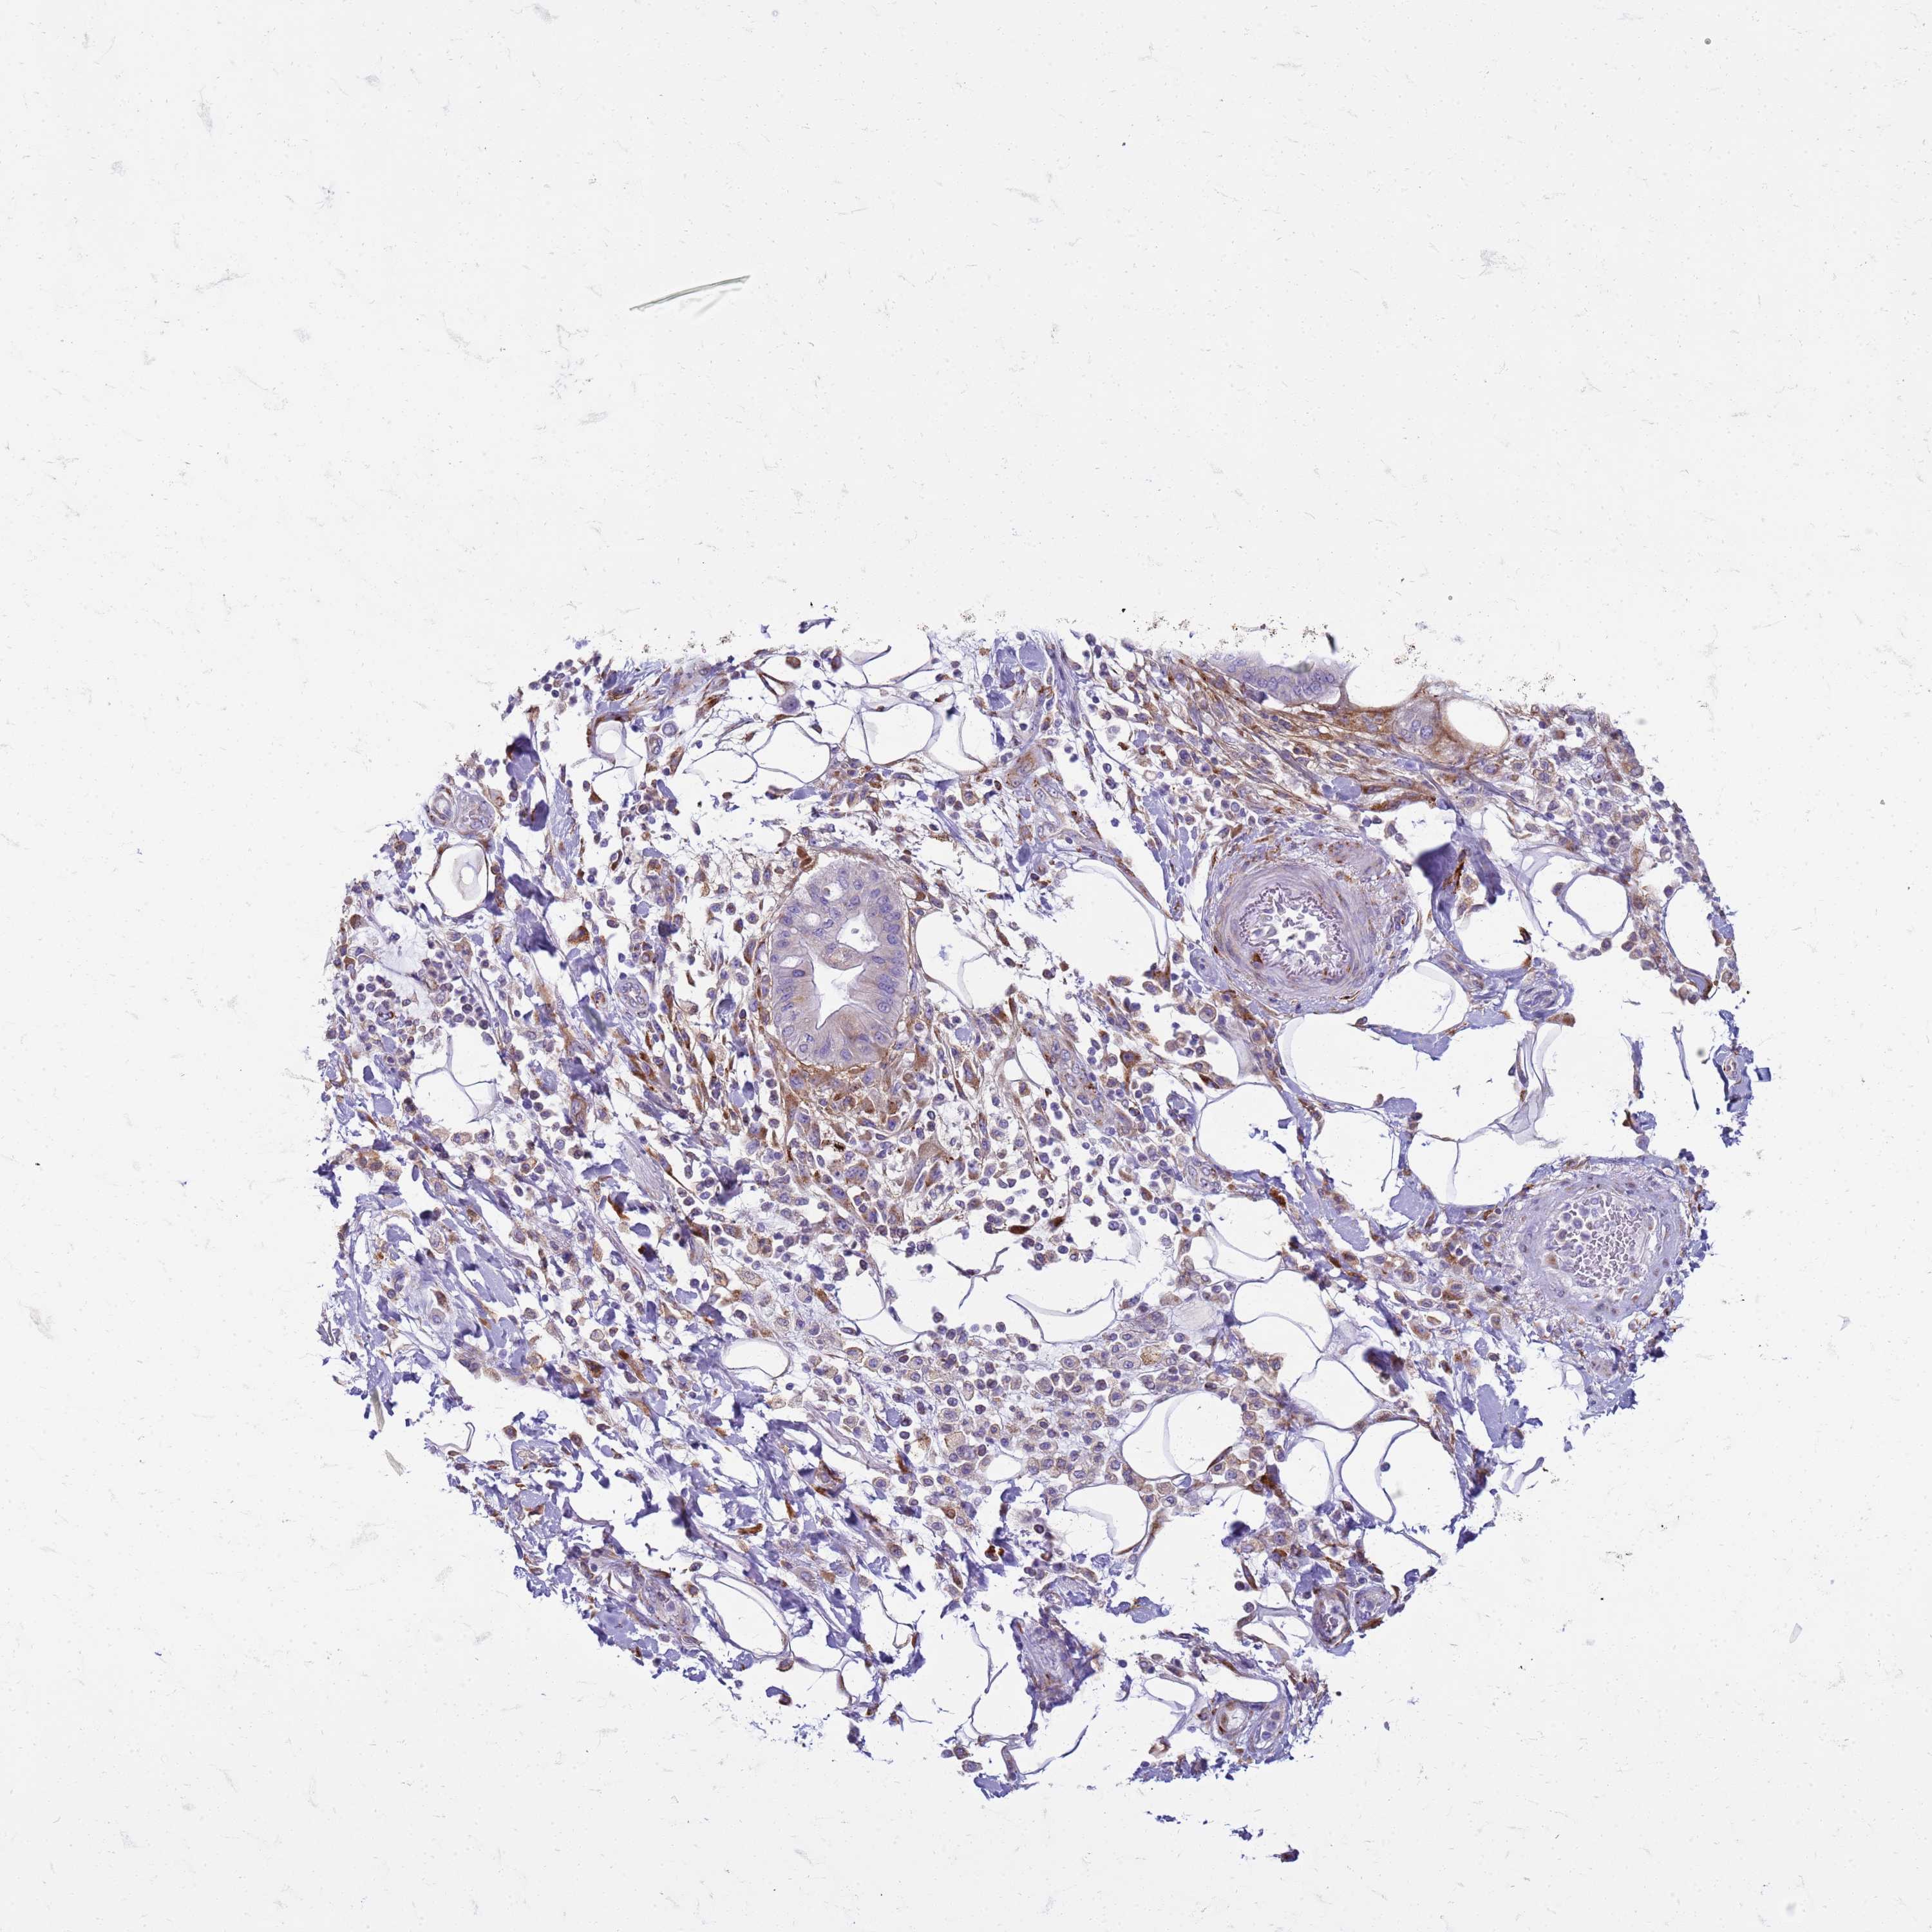

PANCREATIC CANCER - Protein expressioni

A mouse-over function shows sample information and annotation data. Click on an image to view it in a full screen mode. Samples can be filtered based on level of antibody staining by selecting one or several of the following categories: high, medium, low and not detected. The assay and annotation is described here.

Note that samples used for immunohistochemistry by the Human Protein Atlas do not correspond to samples in the TCGA dataset.

Antibody stainingi

Antibody staining in the annotated cell types in the current human tissue is reported as not detected, low, medium, or high, based on conventional immunohistochemistry profiling in selected tissues. This score is based on the combination of the staining intensity and fraction of stained cells.

Each image is clickable and will lead to virtual microscopy that enables deeper exploration of all samples and also displays staining intensity scores, fraction scores and subcellular localization as well as patient and tissue information for each sample.

Antibody HPA046583

Staining

High

Medium

Low

Not detected

Intensity

Strong

Moderate

Weak

Negative

Quantity

>75%

75%-25%

<25%

None

Location

Nuclear

Cytoplasmic/membranous

Cytoplasmic/membranous,nuclear

Adenocarcinoma, NOS

Adenocarcinoma, metastatic, NOS